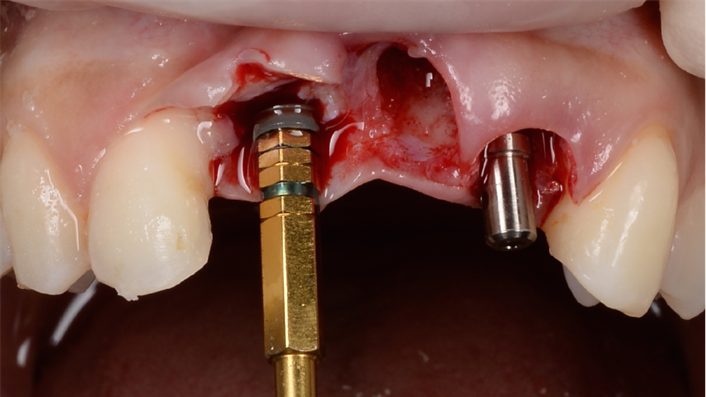

Clinical case: BPET PREDICTABILITY - State-of-the-Art SOCKET SHIELD

- Courtesy of Dr. Howard Gluckman, South Africa -

“AnyRidge is perfect for the anterior esthetic zone due to its strong initial stability & fast osseointegration.

Plus, KnifeThread® ensures space maintenance when using the PET/Socket Shield/Root Membrane Technique, showing excellent bone growth.”